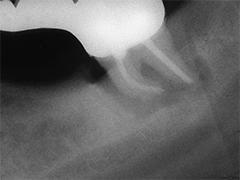

Aufbissempfindlichkeit an 33 veranlasste uns erstmalig in dieser Kieferregion zu röntgen. Mit grossen Augen sahen wir dann an, was uns auch ansah. Einen Knochendefekt dieser Grössenordnung mit seiner schaurigen Aura sieht man zum Glück nicht jeden Tag. Doch, obgleich das Alien dereinst Zahn 34 entsprang, war eine Behandlung nur am Zahn davor durchsetzbar. Dessen Wurzelfüllung erfolgte regulär nach 14 Tagen, neue Terminangebote aber wurden, weil angeblich nicht mehr nötig, verschmäht.

Keine 8 Wochen gingen noch in's Land, bis das mit Macht geschah, was lange schon erwartet war. Das Arbeitsprogramm bestand aus Eröffnung von Zahn 34 und einer Schwellung inkl. Drainage, am nächsten Tag dann noch Aufbereitung des Kanals mit Einlage. 2 Wochen später dann die Füllung plus einem als Resektion deklarierten Auslöffeln des Granu­lationsgewebes durch eine Mini-Öffnung, zu deren Verschluss eine Naht genügte.

3 Aufnahmen sind von 2001, die vierte vom Nov. 2006